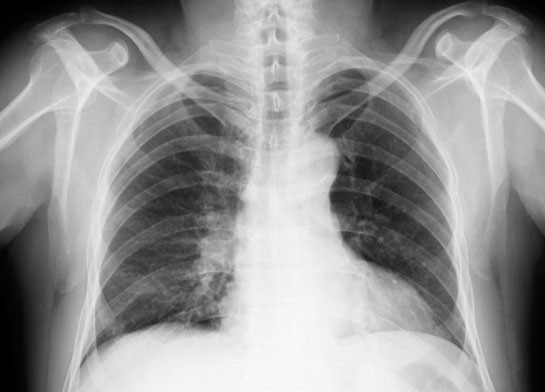

Akciğerdeki tek nodüllerin büyük kısmı (%80) basit sebeplere dayanırken bir kısmı da kanser olabilir. Bu durum araştırmalarla ve bazı durumlarda hastanın üçer ay ara ile çekilen tomografileri ile yapılan takipleriyle ortaya çıkartılır ve buna göre tedavi edilir.Zaman zaman çekilen röntgenlerde akciğerde anormal bir oluşuma rastlanabilir. Doktorlar buna lezyon, nodül, kitle diyebilirler. Kanser herkesin korktuğu bir ihtimal olsa da bu nodüllerin çoğu enfeksiyon, kan damarı anormalliği gibi başka sebeplere dayanır ve kanseröz değildir.

Kan damarı anormallikleri ve romatoid artrit gibi durumlar da akciğerde nodüle yol açabilir. Bazıları zararsızken bazıları tehlikelidir. Neyse ki radyoloji uzmanları akciğerdeki dokunun görüntüsüne bakarak yorum yapabilir ve bu doktorların karar vermesine yardımcı olur.